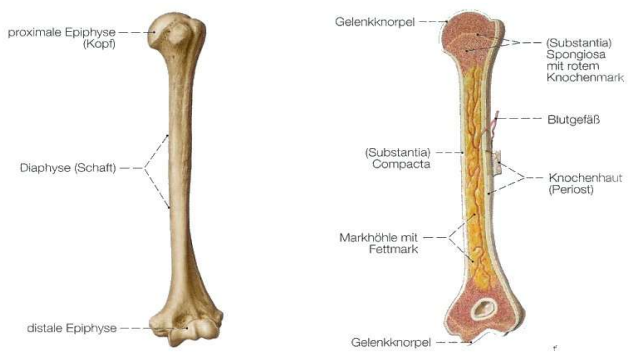

Merkmale Knochengewebe

Hohe Zug- und Druckfestigkeit

Bestandteile:

1/3 Wasser

2/3 organische (Collagen, Eiweiß 1/3) & anorganische Trockensubstanz (Kalksalze 2/3)

Ernährung über Knochenhaut durch Kanäle

Knochen - makroskopischer Aufbau

Knochen - Feinbau